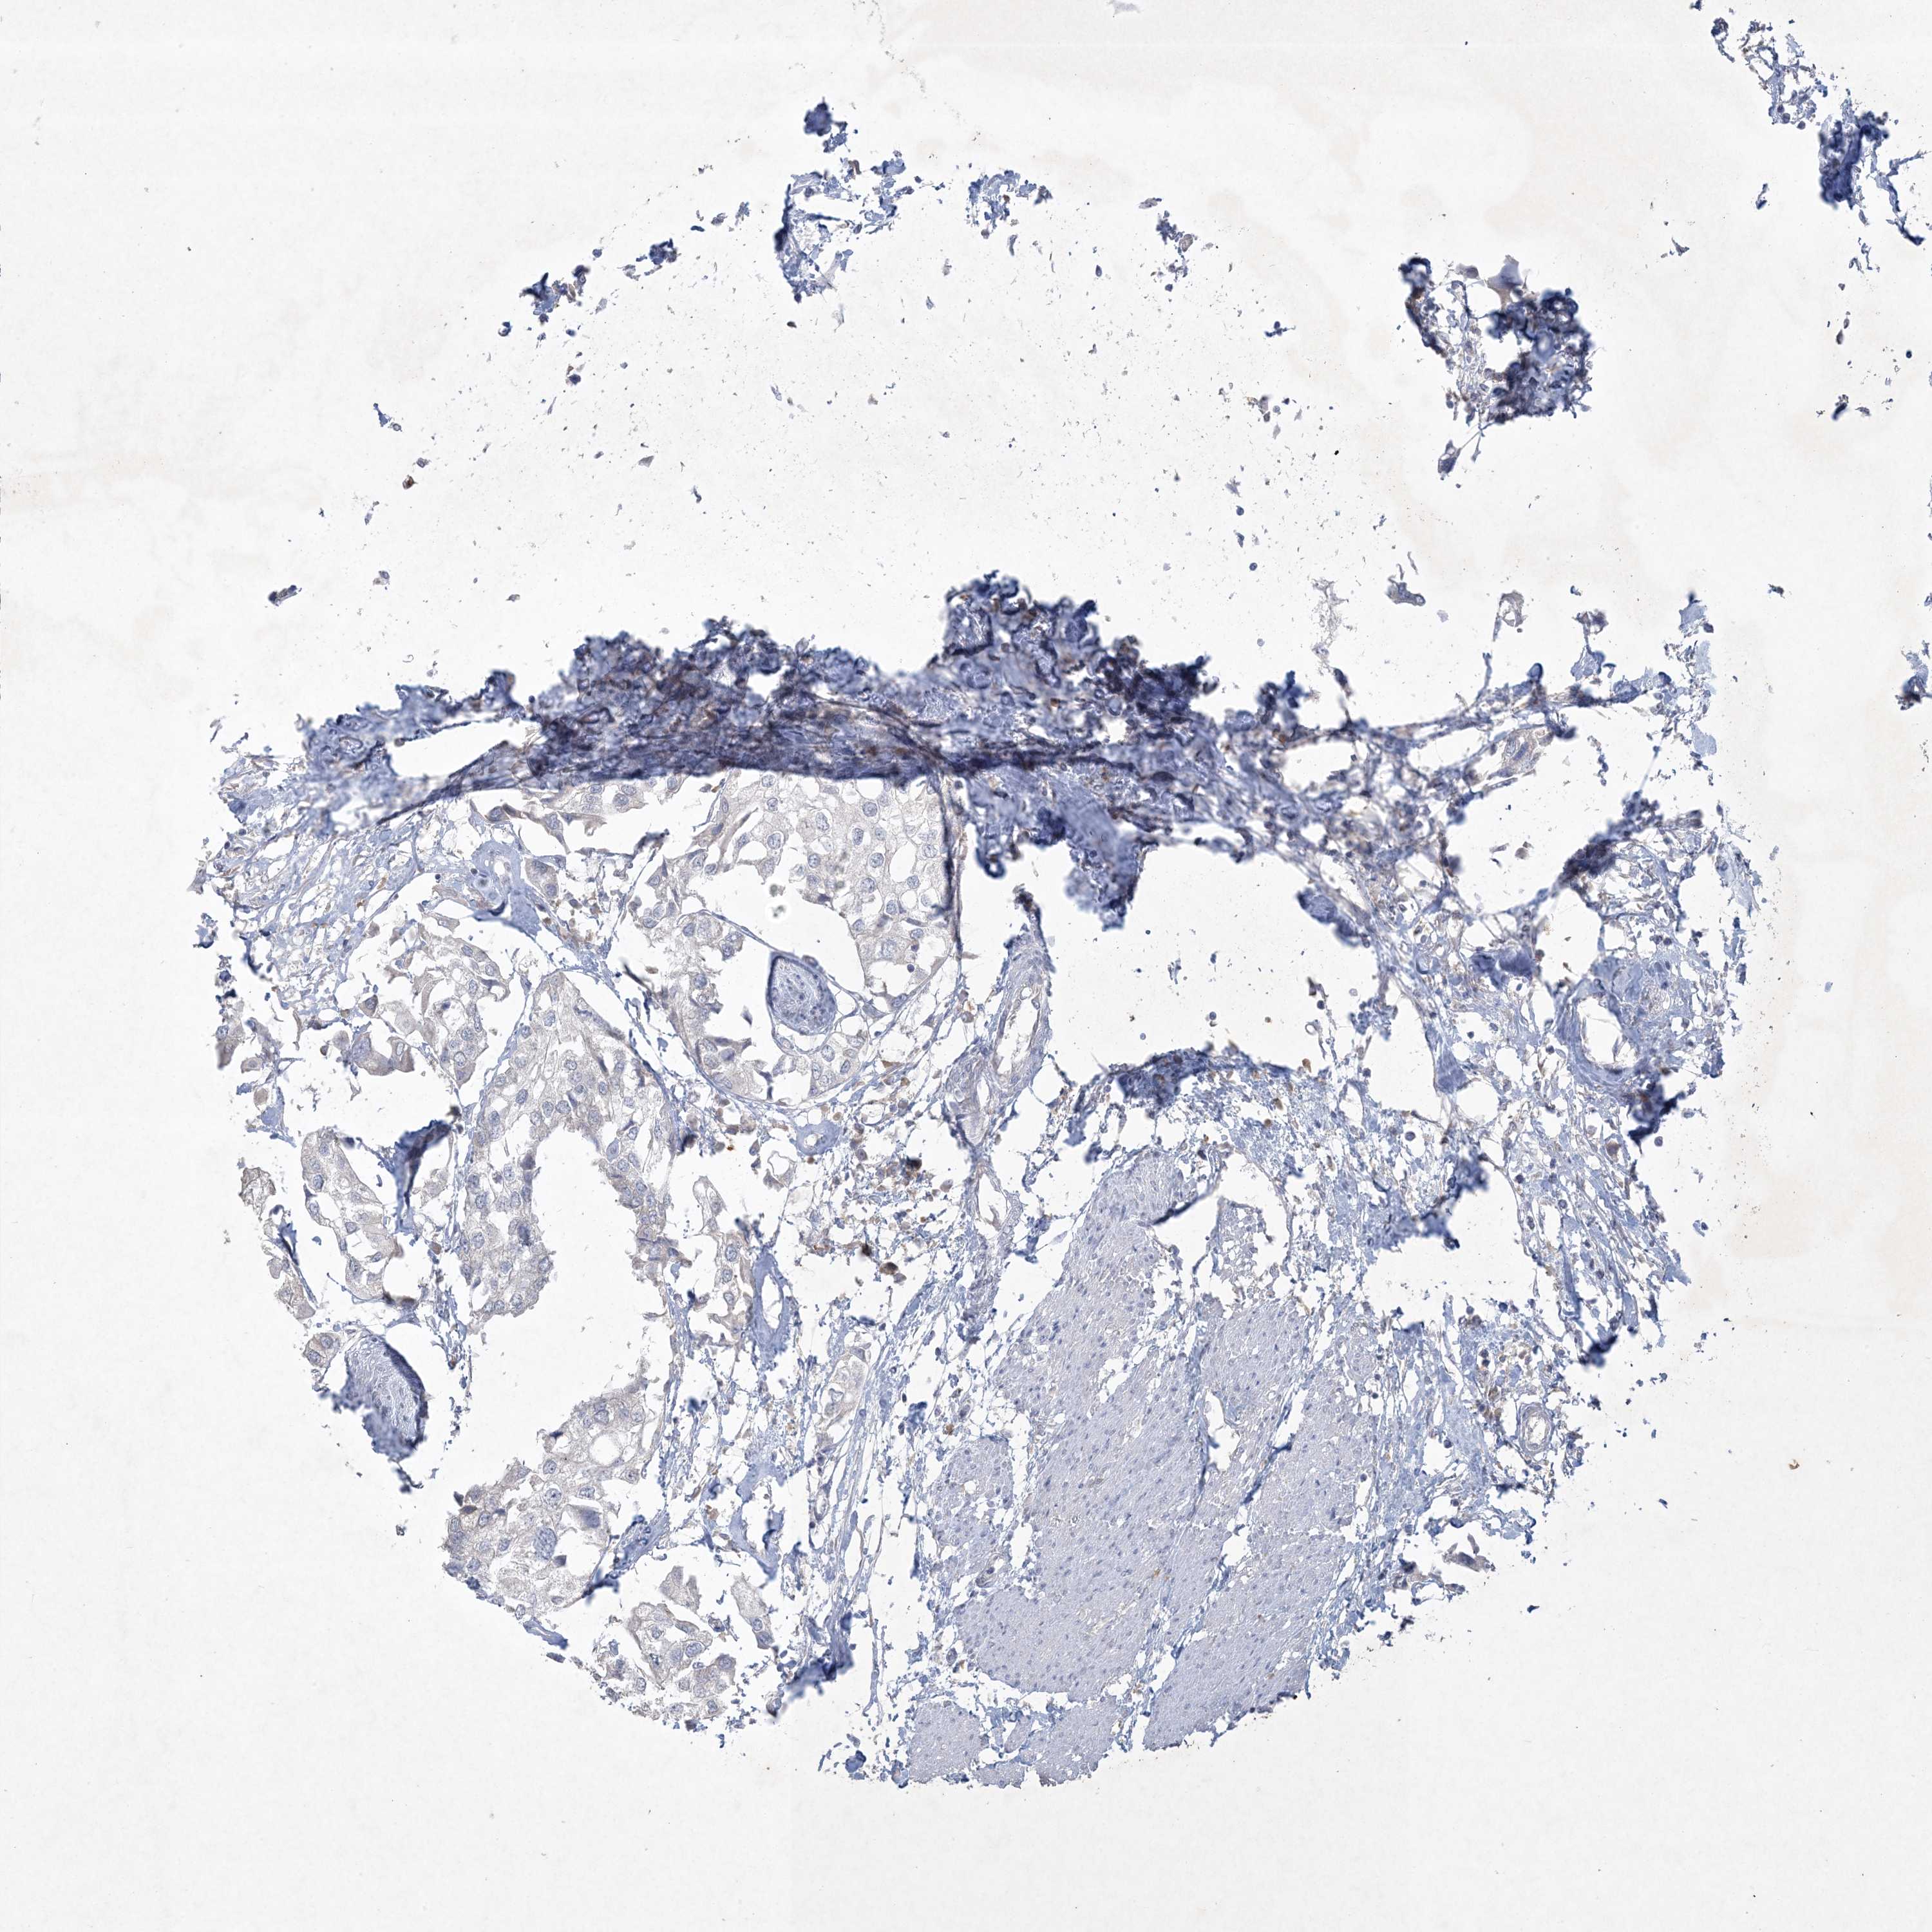

UROTHELIAL CANCER - Protein expressioni

A mouse-over function shows sample information and annotation data. Click on an image to view it in a full screen mode. Samples can be filtered based on level of antibody staining by selecting one or several of the following categories: high, medium, low and not detected. The assay and annotation is described here.

Note that samples used for immunohistochemistry by the Human Protein Atlas do not correspond to samples in the TCGA dataset.

Antibody stainingi

Antibody staining in the annotated cell types in the current human tissue is reported as not detected, low, medium, or high, based on conventional immunohistochemistry profiling in selected tissues. This score is based on the combination of the staining intensity and fraction of stained cells.

Each image is clickable and will lead to virtual microscopy that enables deeper exploration of all samples and also displays staining intensity scores, fraction scores and subcellular localization as well as patient and tissue information for each sample.

Antibody HPA029052

Antibody CAB020944

Urothelial carcinoma, High grade

Urothelial carcinoma, Low grade